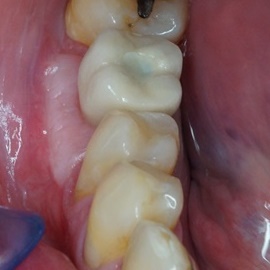

Odbudowa lewego dolnego trzonowca.

Odbudowa prawego dolnego trzonowca.